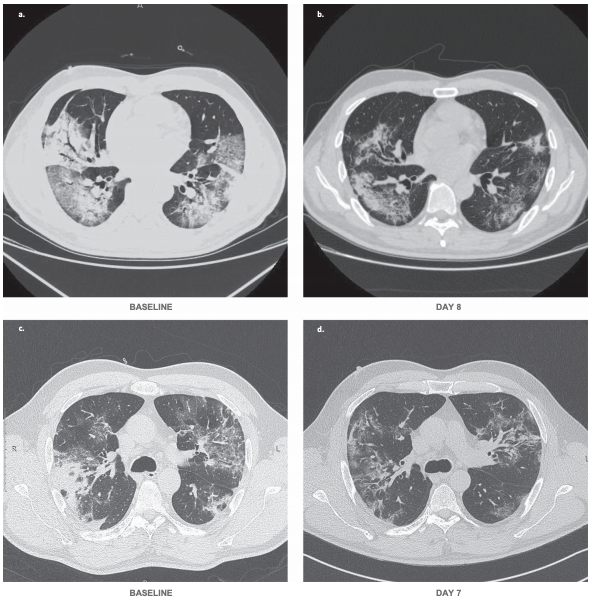

By day 28 of bevacizumab, 92% of patients showed improvement in oxygen-support status, and 65% were discharged from hospital. No patient who received the combination of bevacizumab and standard care showed worsen oxygen-support status or had died after 28 days. In the control group 46% were discharged from hospital by day 28 and three patients had died. Bevacizumab also shortened the duration of oxygen-support to a median of nine days compared with 20 for the standard care group. The researchers describe that patients exhibited reduced lesions shown in CT or X-ray and a normalization of body temperatures. Decreased oxygen supplementation can both improve the health status for individual patients and decrease the healthcare burden.